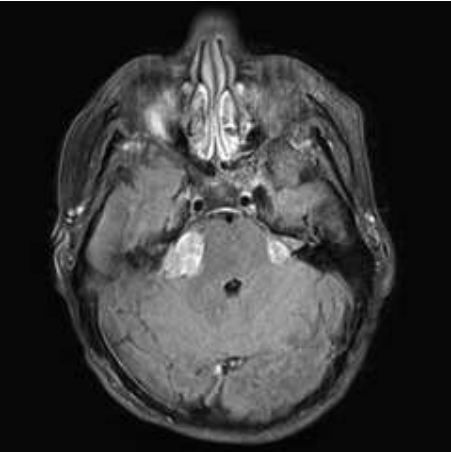

Paciente de 25 anos, sexo masculino, com histórico de perda auditiva e alterações do equilíbrio há 3 meses. A avaliação com ressonância magnética demonstrou a seguinte imagem:

Assinale a alternativa correta